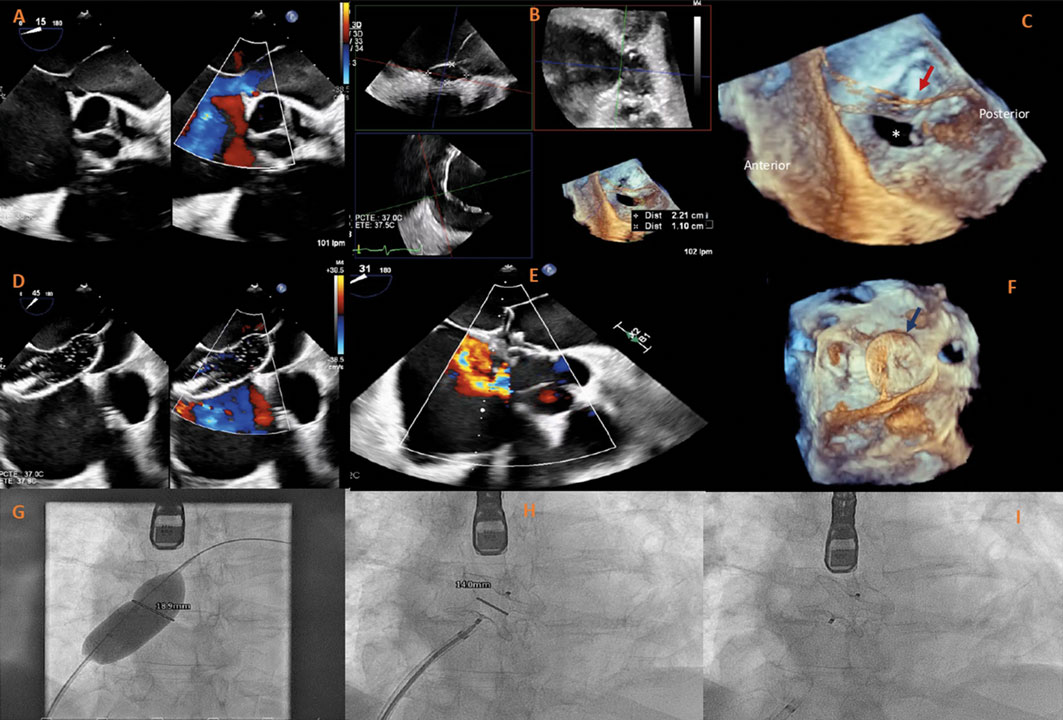

Varón de 67 años con signos de insuficiencia cardiaca derecha secundaria a comunicación interauricular (CIA) con dilatación ventricular derecha, shunt izquierda-derecha significativo (Qp/Qs 1,5) y sin hipertensión pulmonar precapilar significativa (presión arterial pulmonar media, 26 mmHg; resistencia vascular pulmonar, 2 UW). La ecocardiografía transesofágica tridimensional (ETE 3D) reveló la presencia de un cor triatriatum sinister (CTS) con una membrana que se extendía desde el extremo superior y posterior de la fosa oval hasta la cresta pulmonar, con múltiples fenestraciones, la mayor de 24 mm (figura 1A). Se confirmó la presencia de una CIA tipo ostium secundum de 22 × 11 mm, con el borde posterior parcialmente recubierto por la membrana (figura 1B-C). Como el paciente era técnicamente apto y presentaba un riesgo quirúrgico elevado en un contexto de cirrosis, se optó por un abordaje percutáneo. La intervención se realizó bajo guiado simultáneo por ETE 3D y fluoroscopia, la CIA se cruzó con una guía de 0,035 pulgadas y un catéter multipropósito, la medición con balón confirmó la presencia de un defecto de 20 mm y, por último, se implantó con éxito un oclusor septal Amplatzer de 24 mm (Abbott Structural Heart, Estados Unidos) (figura 1D-F). La ETE confirmó la correcta posición del dispositivo, sin shunt residual ni obstrucción del flujo en la aurícula izquierda. Se obtuvo el consentimiento informado del paciente.

Figura 1.

El CTS es una malformación cardiaca poco frecuente que puede coexistir con la CIA tipo ostium secundum en hasta el 33% de los pacientes. Aunque el cierre percutáneo es el método de elección en anatomías favorables, la presencia de CTS puede complicar el despliegue del dispositivo por la definición inadecuada de los márgenes, con el consiguiente mayor riesgo de inestabilidad y embolización del dispositivo. En este caso, el cierre de la CIA fue especialmente complejo, ya que el borde posterior estaba en continuidad directa con la membrana auricular, lo cual planteaba dudas sobre la adecuada aposición del dispositivo. El presente caso pone de manifiesto lo importantes que son las técnicas de imagen avanzada como la ETE 3D en anatomías complejas, ya que permiten una planificación precisa de la intervención y un guiado en tiempo real para garantizar el éxito de la intervención.